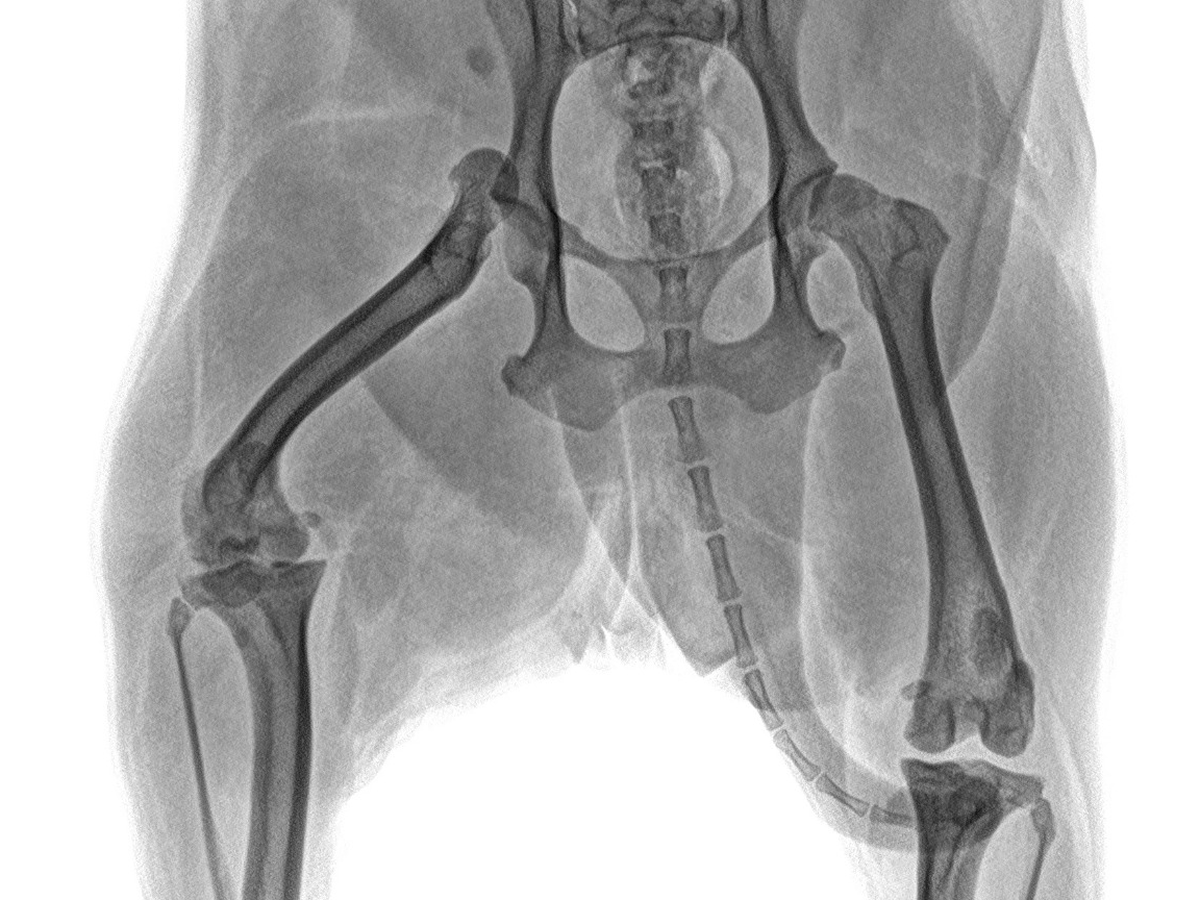

El pasado 14 de noviembre, en mi domicilio, un vecino atropelló accidentalmente a Dalia y se dio a la fuga, dejándole una luxación en una de sus patitas. La lesión fue tan grave que requirió una cirugía ortopédica inmediata. Hasta el 22 de noviembre, los gastos médicos acumulados llegaron a casi $40,000 MXN, los cuales logré cubrir parcialmente gracias al apoyo de amigos y familiares.

Seguimos al pie de la letra el tratamiento indicado por los veterinarios de Animal Home San Jerónimo, pero lamentablemente, el 10 de diciembre recibí una noticia devastadora: además de la luxación, Dalia presenta una rotura de ligamento cruzado y posibles daños en los ligamentos laterales.